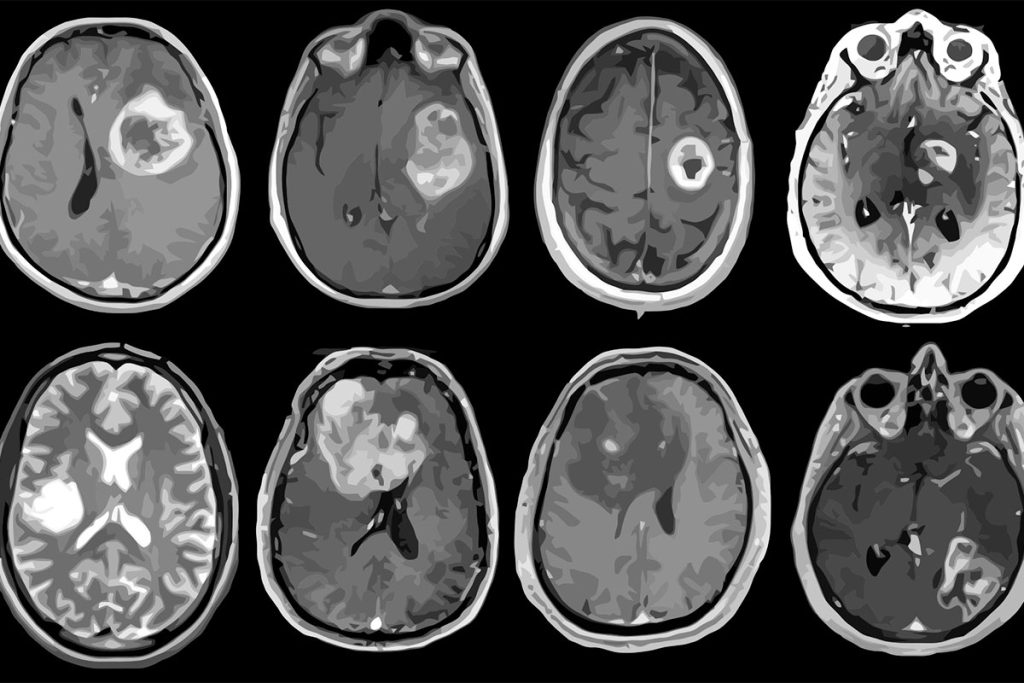

The study, in JAMA Network Open, looked at cancer records from 1992 to 2018 for 3.8 million people in the U.S. They checked cases of cancer that spread to other parts of the body. They compared Generation X to older groups like Baby Boomers and the Silent Generation. The study found that some cancers, like colon, rectal, thyroid, ovarian, and prostate cancers, are getting more common even though medicine is getting better.

Rosenberg and Adalberto Miranda-Filho think more people in Generation X will get certain cancers. Thyroid, kidney, rectum, and colon cancers will go up. Women will have more pancreatic, ovarian, and endometrial cancers. Men will get more prostate cancers and leukemia. Lung cancer will go down for everyone. Men will see fewer liver and gallbladder cancers. Women will have less cervical cancer.

Scientists are trying to figure out why cancer rates are going up. They think diet, exercise, and being overweight might be reasons. Other reasons are still unknown. Chan is leading a study on young people who get cancer without family history or known risks.

Food processing changes and environmental exposures like pollution might play a role. Changes in gut bacteria may also influence cancer rates. Researchers are studying if cancers in young people are biologically different.